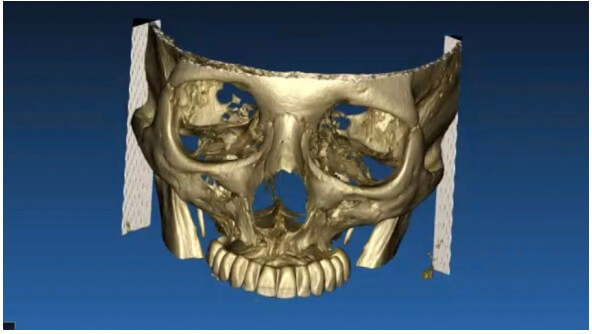

Paciente con edentulismo completo y reabsorción avanzada en maxilar superior.

Rechaza opción removible.

Se planifica rehabilitación completa con 4 implantes Zygoma.

Planificación 3D y confección de férulas quirúrgicas para abordaje guiado.